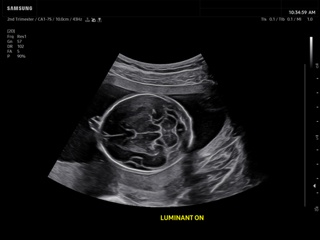

Atlas of ultrasound images - obsterics

In the section "Оbsterics" of atlas the results of ultrasonic examinations of pregnant women with different durations of gestation are represented. Here you can see images of internally organs, cerebrum, cordis and the sex of the fetus, the sonograms of multiple pregnancy, the blood flow in placenta and umbilical cord, defects of fetal`s development, etc.